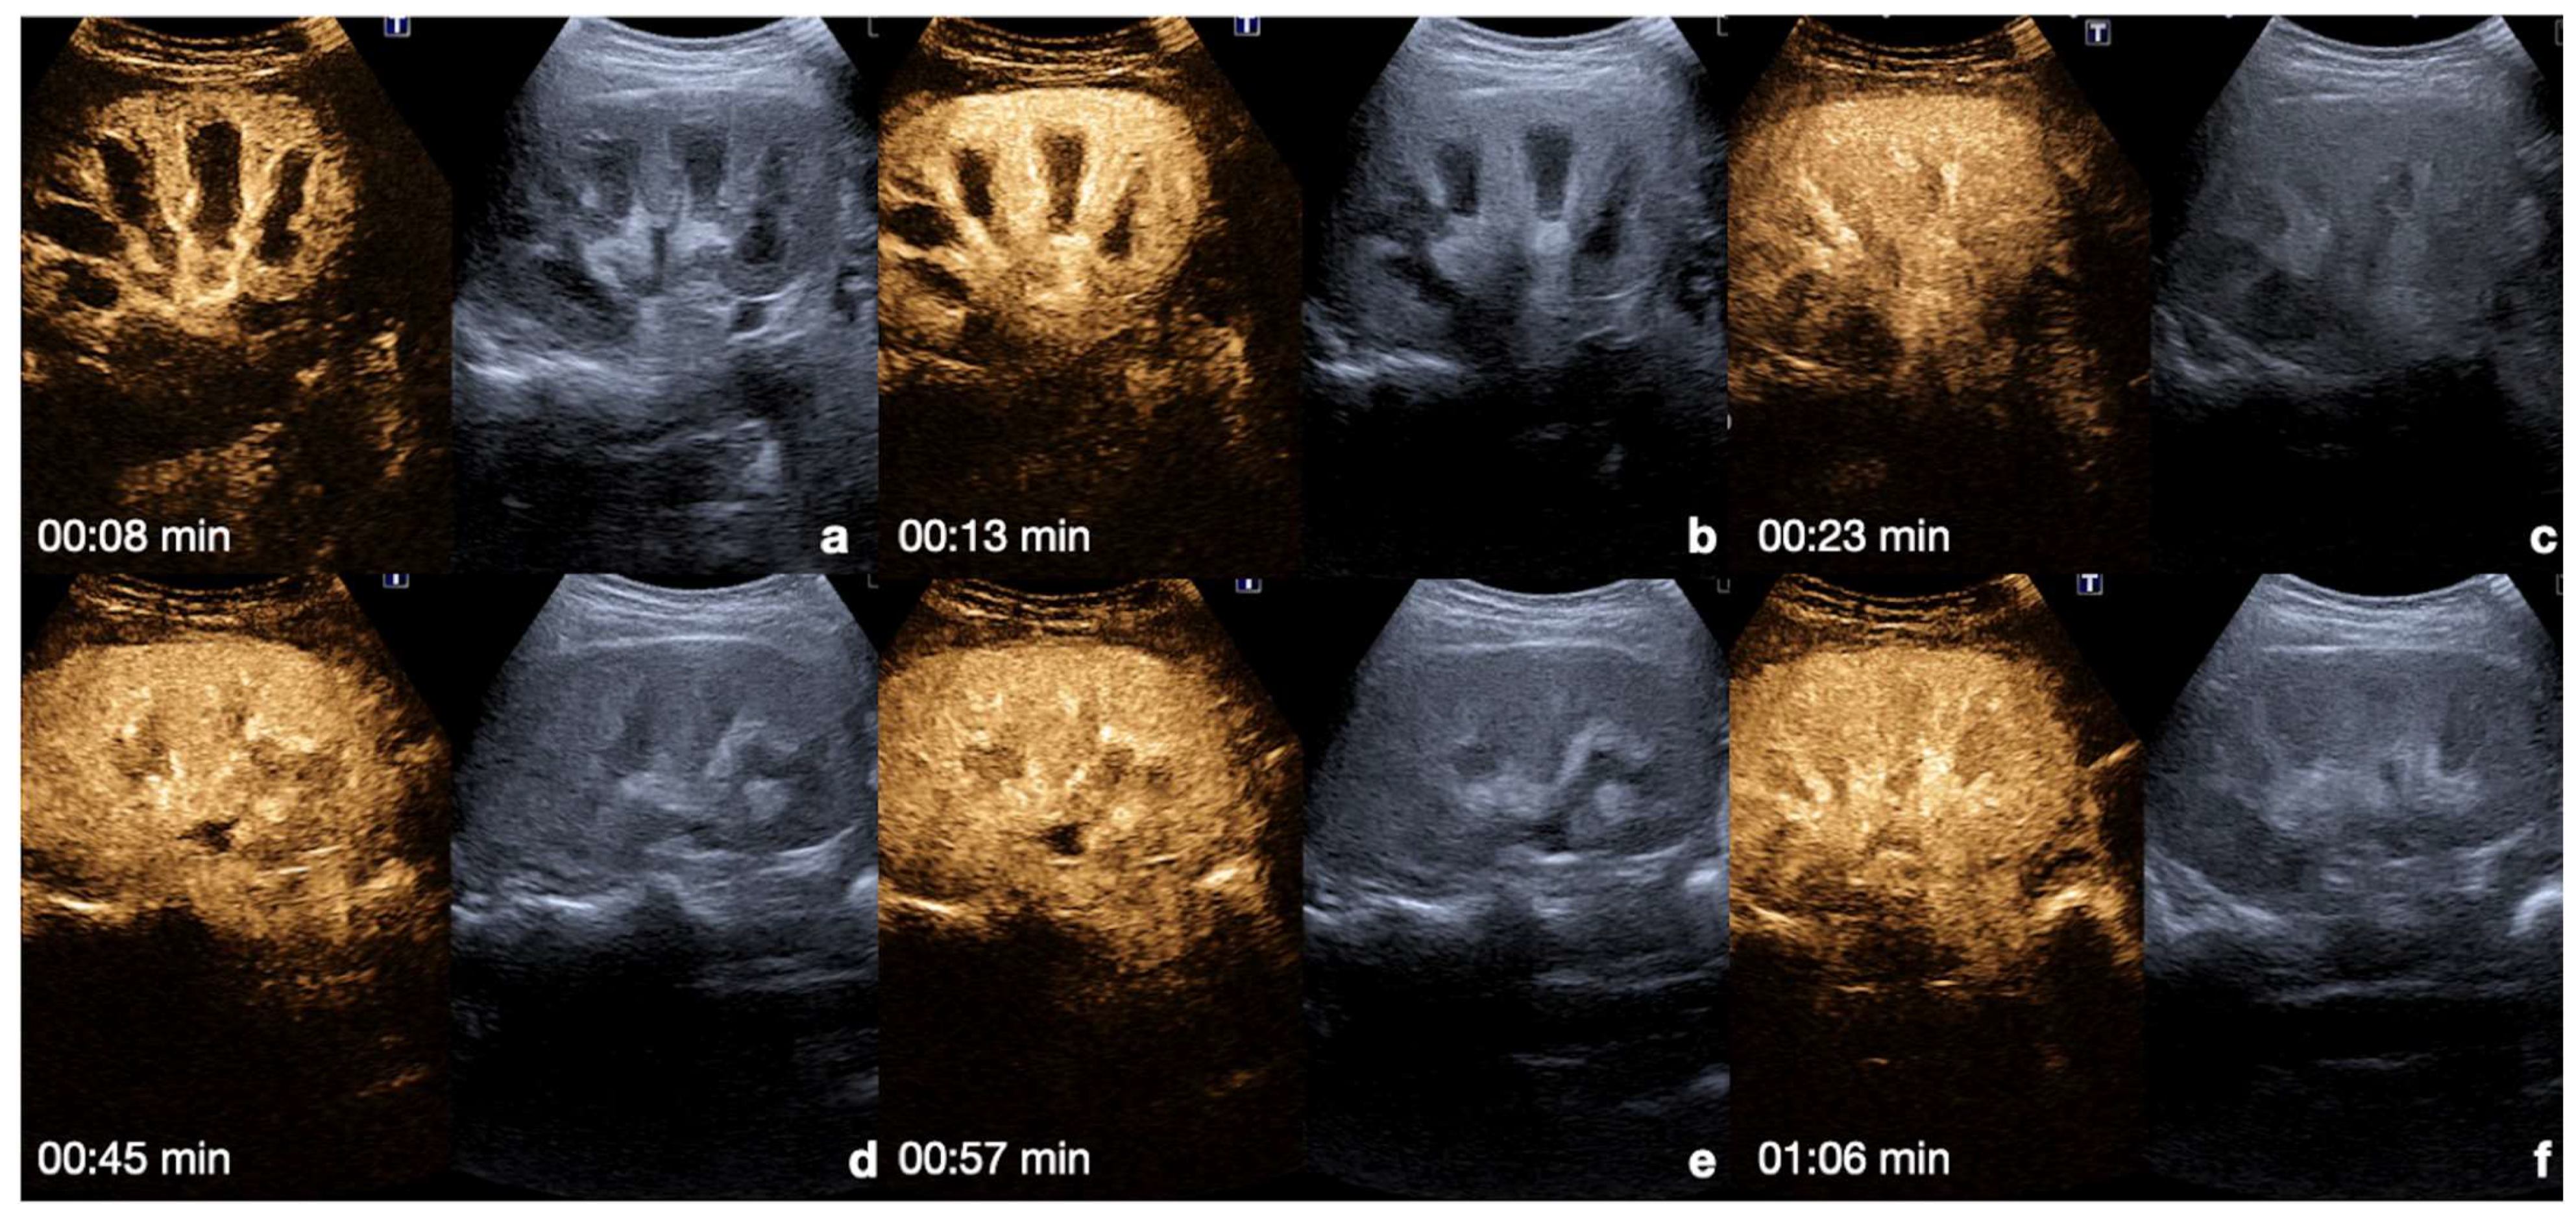

Kidney: the cortex enhances quickly and intensely after the injection, while the pyramids enhance from the periphery to the center in approximately 30 s [13,26]. The optimal time window for renal parenchymal injury assessment is up to 2.5 min following injection, as this is when maximum enhancement of the kidney can be observed [27,30] (Figure 4).

Figure 4.

CEUS findings in a normal kidney (a–f). Note the progressive physiological enhancement of the cortex and the medulla. Adopted from ref. [30], 2021, Iacobellis, F.; et al.

UCA does not accumulate in the pelvicalyceal system; therefore, no excretory phase will occur.